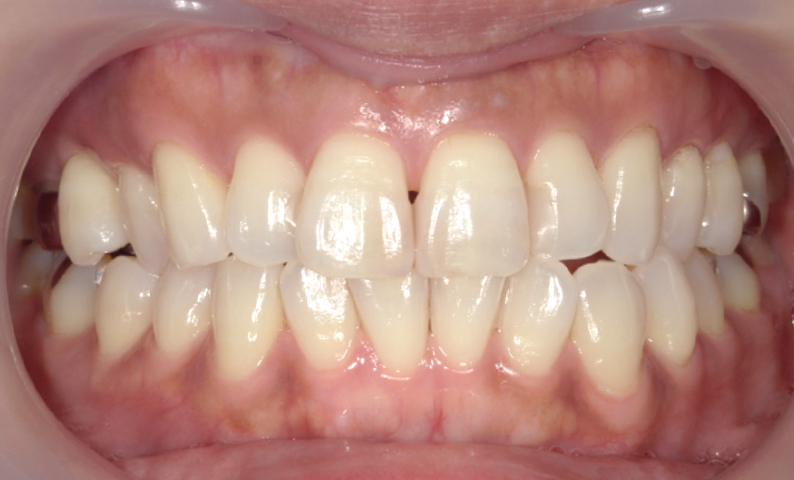

症例_001 前歯「捻転歯」症例

治療期間:6ヶ月金額:48万円+税20代女性少しのねじれ捻転歯下の八重歯

| Before | After |